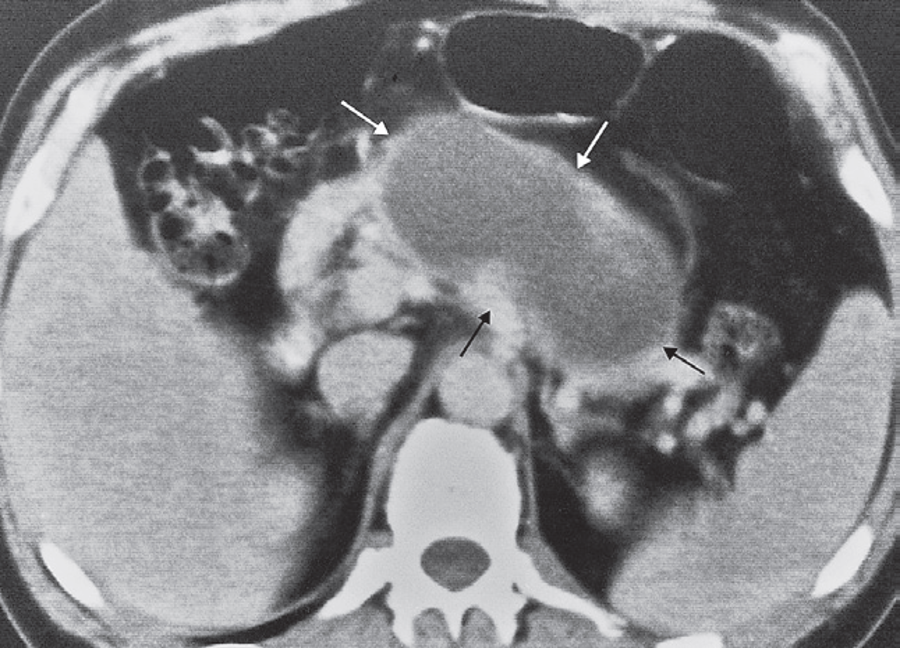

Pancreatic pseudocyst

CT scan showing a large cyst; fluid density arising within the pancreas (arrows).